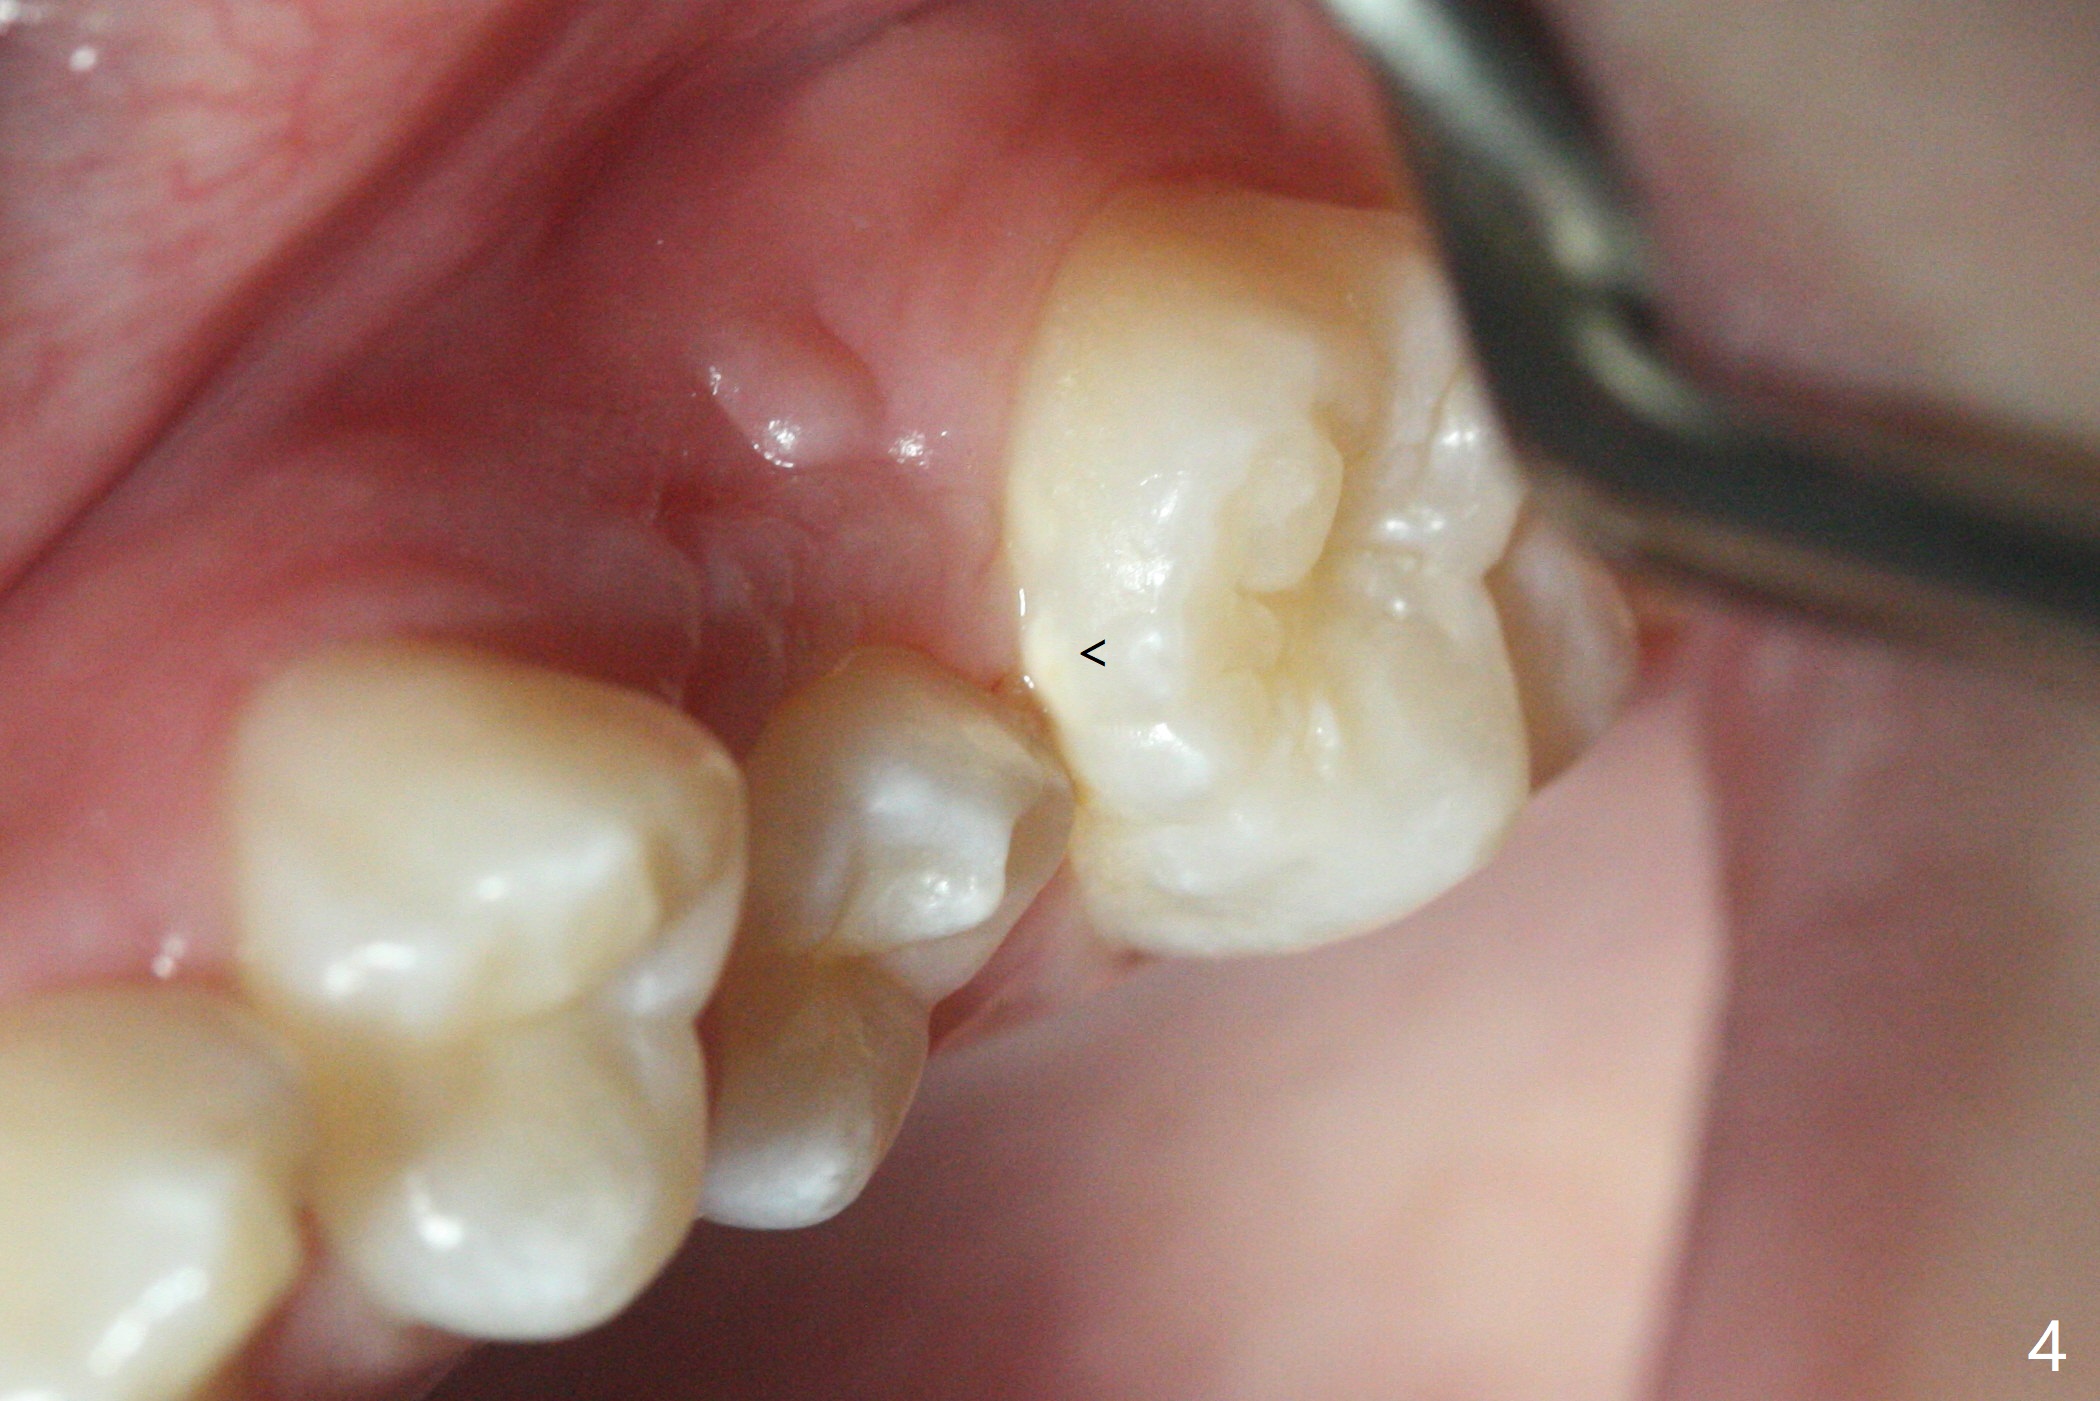

10岁半女孩上颌第二乳磨牙远中龋好像造成第一恒磨牙近中龋(图一)。要求妈妈当乳磨牙脱落时,带她回来补牙。由于新冠病毒,女孩1年3个月后才回来,右上第二前磨牙已经基本完成萌出,右上6近中龋被掩盖了(图二),而左侧前磨牙腭侧部分萌出(图三,四),磨牙近中龋(表现为脱钙,图四:箭头)正好暴露。塞入gingival retraction cord(图五:C)和wedge (W),去龋,填入树脂,两牙之间通过牙线(F),光固化。之后不需要抛光。